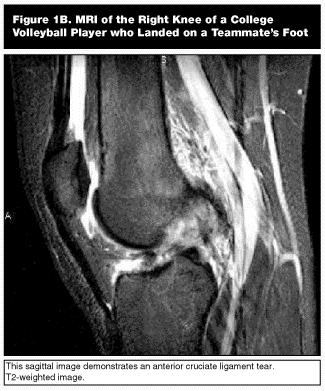

Radiography of the knee is essential in these injuries to evaluate for fractures or avulsed ligament insertions.9,10,14,17,19 Stress radiographs can also be helpful in diagnosing ligament instability. MRI can be very useful in evaluating the knee ligament structures although it is not essential if a careful physical examination can be performed.9,10,12 (see Figures 1A-B). MRI is also sensitive in diagnosing associated meniscal pathology in addition to ligamentous injuries.9,14,17,20,21